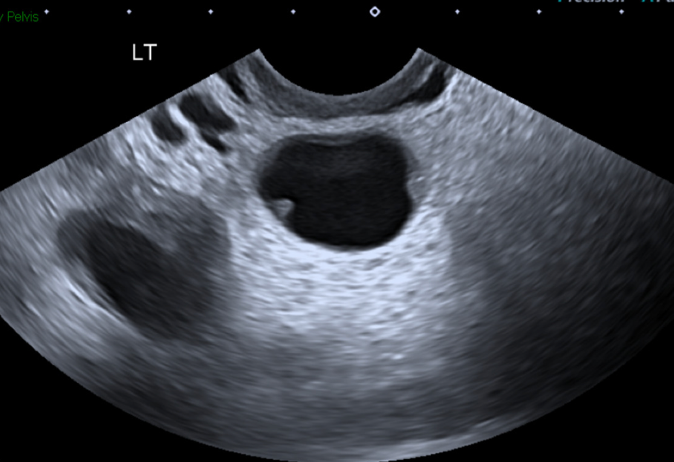

There is hydronephrosis of the left kidney. The right kidney is normal-appearing. Bladder views incidentally revealed a large complex, fluid-containing lesion in the pelvis (color doppler negative).

Case continued: Labs were significant for leukocytosis. Urine pregnancy test was negative and urinalysis did not show evidence of a UTI. CT scan showed a mixed solid and cystic lesion within the left adnexa concerning for a tubo-ovarian abscess and left-sided hydronephrosis likely due to external ureteral compression by the left adnexal mass. Transvaginal ultrasound demonstrated 8 cm tubo-ovarian abscess with dense adhesions between the sigmoid colon and bladder. The patient was started on ceftriaxone, doxycycline, and metronidazole. She was admitted to gynecology and ultimately underwent IR-guided drainage of the abscess.